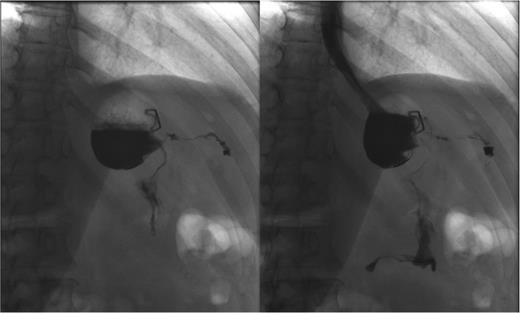

Three months later, patient presented with recurrent abdominal wall abscess. A GS demonstrated ongoing leak from the GCF (Fig. 2). On 8 September 2014, she underwent a laparoscopic fistulectomy. The fistula tract was transected and the gastric part of fistula excised. The spleen was involved in the inflammatory cavity, but splenectomy was eventually avoided. Since the gastric sleeve was healthy, it was decided not to resect the remaining stomach. No evidence of a fistula was detected on a GS performed at the 6-week postoperative check (Fig. 3).

Persistent leak detected with GS. The images clearly show persistence of the leak along with the fistula tract. One of the endoscopic clips previously positioned is also visible.